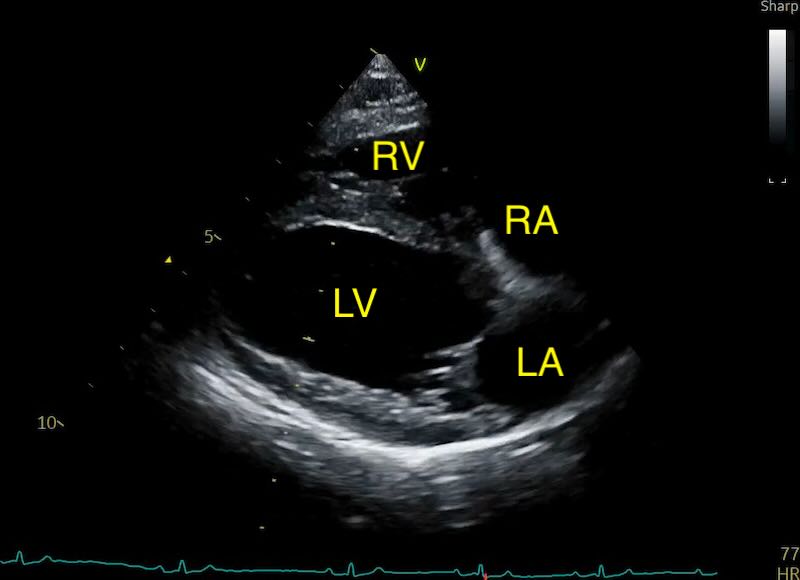

The View: Acquisition of the “Heart Homepage”

The LAD is measured using the Right Parasternal Long-Axis 4-Chamber view (RPLA4Ch). This is often called the “heart homepage” because it allows for a comprehensive subjective and objective assessment of all four chambers simultaneously. See our article on echo views here.

As a quick summary:

- Acquisition: With the dog in right lateral recumbency, place the probe at the point of the strongest apical beat. Align the probe parallel to the long axis of the heart, with the transducer mark (and your forefinger) pointed toward the dog’s head.

- Optimisation: Aim to maximise the length of the left ventricle, ensuring the apex is visible and the mitral valve is clearly defined. Avoid any aorta showing (5 chamber view).